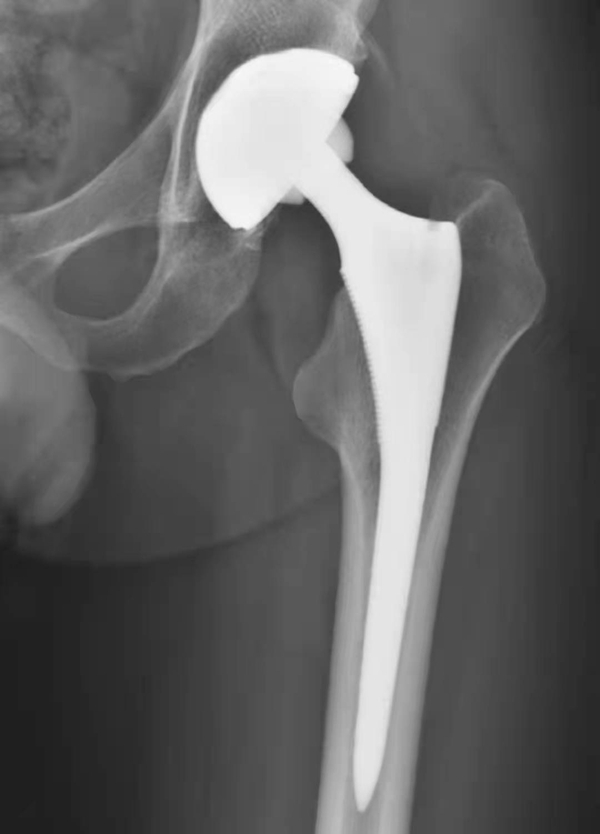

图1 人工髋关节置换术后正常X线表现

图2 无菌性松动

平片,示右侧股骨上段骨质疏松,人工股骨柄周围明显骨质吸收,透亮带明显增宽,髋臼杯位置未见改变